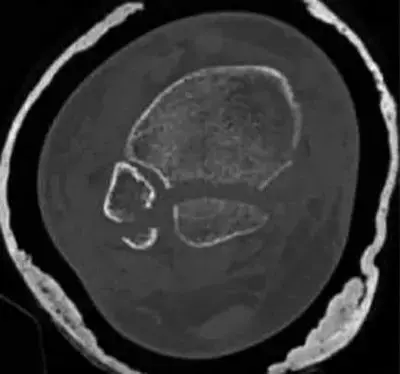

ساركوما العظام: دليلك الشامل للتشخيص والعلاج والتعافي في صنعاء مع الأستاذ الدكتور محمد هطيف

دليلك الشامل لتشخيص وعلاج ساركوما العظام في صنعاء مع الأستاذ الدكتور محمد هطيف. احصل على رعاية متخصصة بأحدث التقنيات الجراحية لضمان أفضل نس…